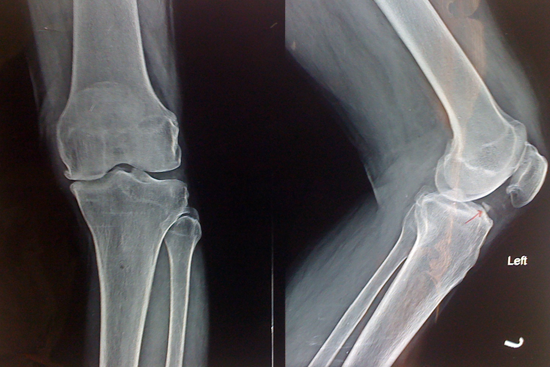

Knee Deformity